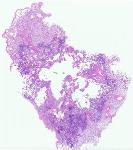

10535 |

左颈部淋巴结 |

男, 34岁, 既往史:否认肝炎史,否认结核史,否认梅毒史,否认HIV史。

... |

复旦大学附属华山医院 |

有诊断 |